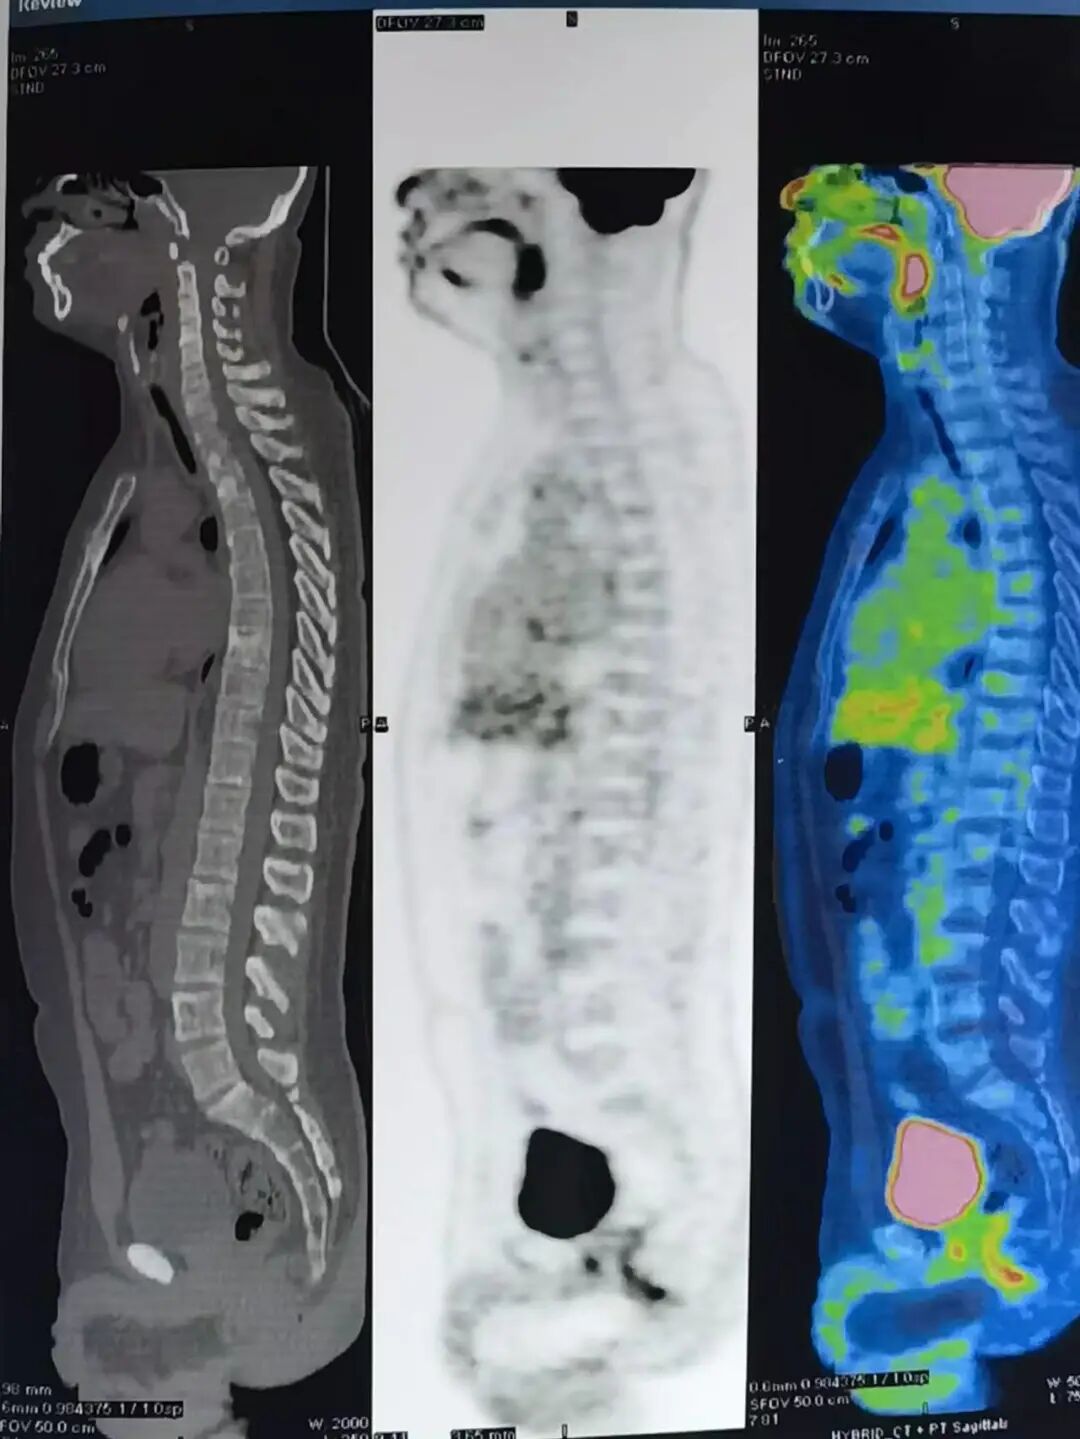

返回天津后,我立刻前往医院复查,复查的结果让我的心重重沉下:肾癌复发了。检查报告摆在眼前,好运没有再次眷顾我,还发现了多发肝转移,肋骨、骨盆、脊柱等多处骨转移。

2021年治疗前PET-CT检查结果

我被迫再次离开自己的工作岗位——即使没有医学背景,我也知道,自己的情况十分危急,不容乐观。于是,我迅速找到了天津肿瘤医院泌尿肿瘤科姚欣主任进行住院治疗。

多发肝转移、多处骨转移……2021年的重病再发,与2019年已不可同日而语。“这次重病,最痛苦的就是骨痛,让我彻夜难眠、坐立不安。”真正是“痛到骨子里”,只有定时口服吗啡才能缓解一二。